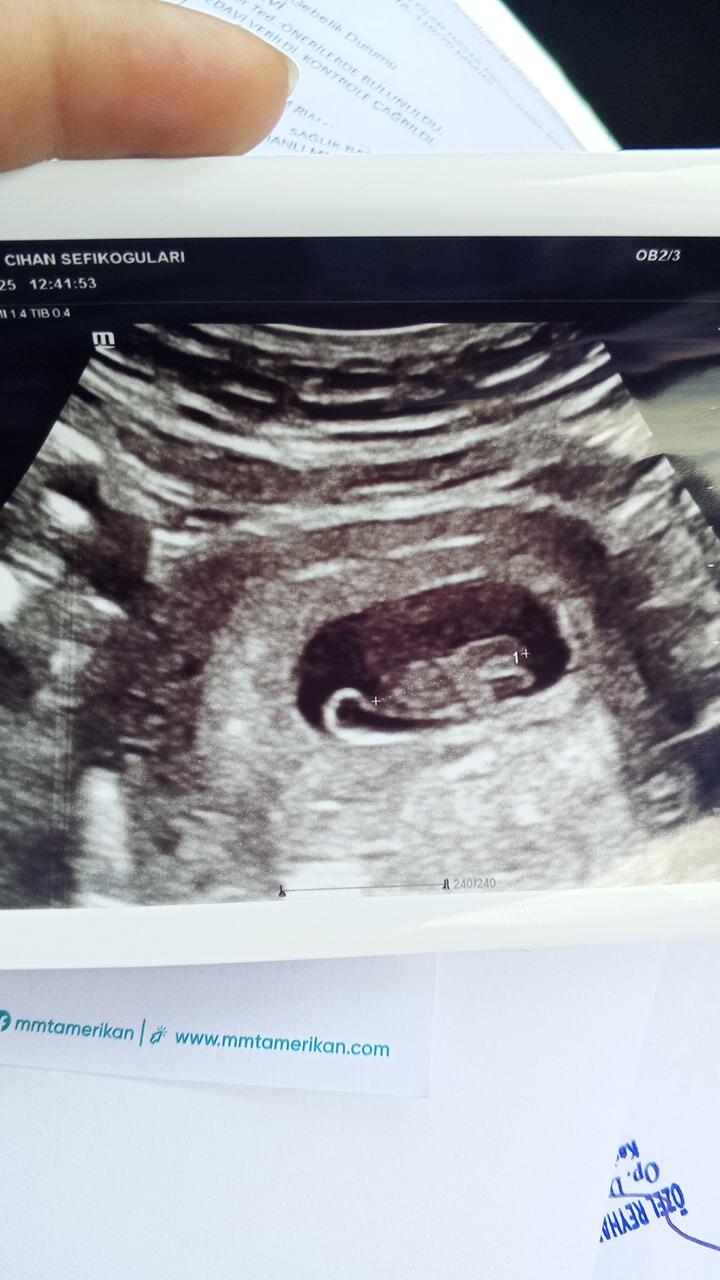

Ben kesenin fotosunu attım gözüküyor mu bilmiyorum sizce cinsiyeti bellimi

Kız gibi duruyor Allah sağlıkla kucağına almayı nasip etsin inşallah ![]()

Kız bu benim tahminim Hayırlı evlat olsun inşallah ![]()

Kız kesesi gibi duruyor sağlıkla gelsin ![]()

Sağlıcakla kucağına al canım. Bence erkek.

erkek gibi, sağlıkla gelsin bebişiniz.